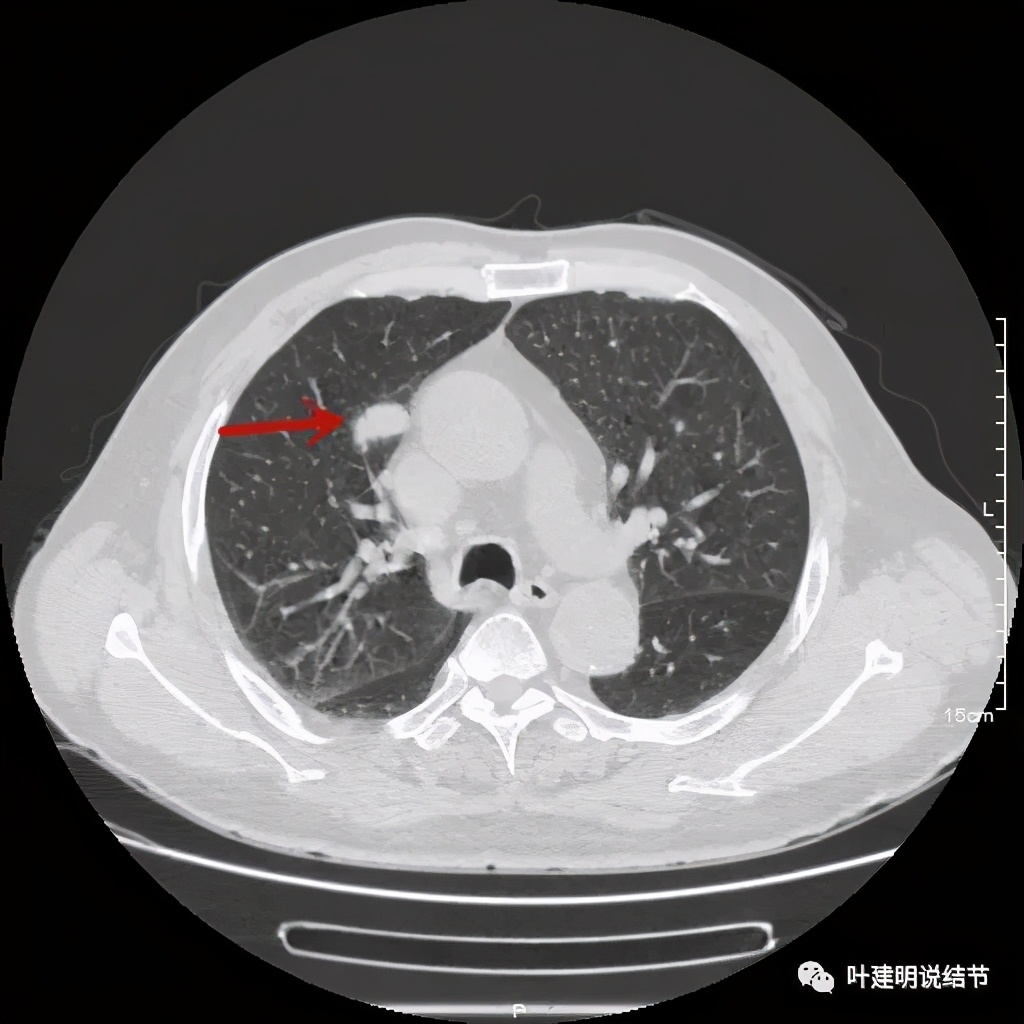

上图也示病灶密度不均,但边缘过于光滑(绿色);支气管似有截断(粉色);局部有点状钙化(蓝色)

病灶在上图层面似见支气管也是贴壁的。那么增强后又是如何呢?